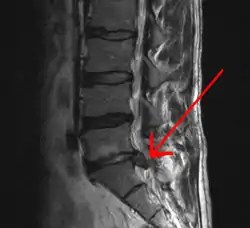

In most episodes, a specific underlying cause is not identified or even looked for, with the pain believed to be due to mechanical problems such as muscle or joint strain.[1][4] If the pain does not go away with conservative treatment or if it is accompanied by "red flags" such as unexplained weight loss, fever, or significant problems with feeling or movement, further testing may be needed to look for a serious underlying problem.[5] In most cases, imaging tools such as X-ray computed tomography are not useful and carry their own risks.[9][10] Despite this, the use of imaging in low back pain has increased.[11] Some low back pain is caused by damaged intervertebral discs, and the straight leg raise test is useful to identify this cause.[5] In those with chronic pain, the pain processing system may malfunction, causing large amounts of pain in response to non-serious events.[12]

An intervertebral disc has a gelatinous core surrounded by a fibrous ring.[34] When in its normal, uninjured state, most of the disc is not served by either the circulatory or nervous systems – blood and nerves only run to the outside of the disc.[34] Specialized cells that can survive without direct blood supply are in the inside of the disc.[34] Over time, the discs lose flexibility and the ability to absorb physical forces.[26] This decreased ability to handle physical forces increases stresses on other parts of the spine, causing the ligaments of the spine to thicken and bony growths to develop on the vertebrae.[26] As a result, there is less space through which the spinal cord and nerve roots may pass.[26] When a disc degenerates as a result of injury or disease, the makeup of a disc changes: blood vessels and nerves may grow into its interior and/or herniated disc material can push directly on a nerve root.[34] Any of these changes may result in back pain.[34]

Tests

Imaging is indicated when there are red flags, ongoing neurological symptoms that do not resolve, or ongoing or worsening pain.[5] In particular, early use of imaging (either MRI or CT) is recommended for suspected cancer, infection, or cauda equina syndrome.[5] MRI is slightly better than CT for identifying disc disease; the two technologies are equally useful for diagnosing spinal stenosis.[5] Only a few physical diagnostic tests are helpful.[5] The straight leg raise test is almost always positive in those with disc herniation.[5] Lumbar provocative discography may be useful to identify a specific disc causing pain in those with chronic high levels of low back pain.[43] Similarly, therapeutic procedures such as nerve blocks can be used to determine a specific source of pain.[5] Some evidence supports the use of facet joint injections, transforminal epidural injections and sacroilliac injections as diagnostic tests.[5] Most other physical tests, such as evaluating for scoliosis, muscle weakness or wasting, and impaired reflexes, are of little use.[5]